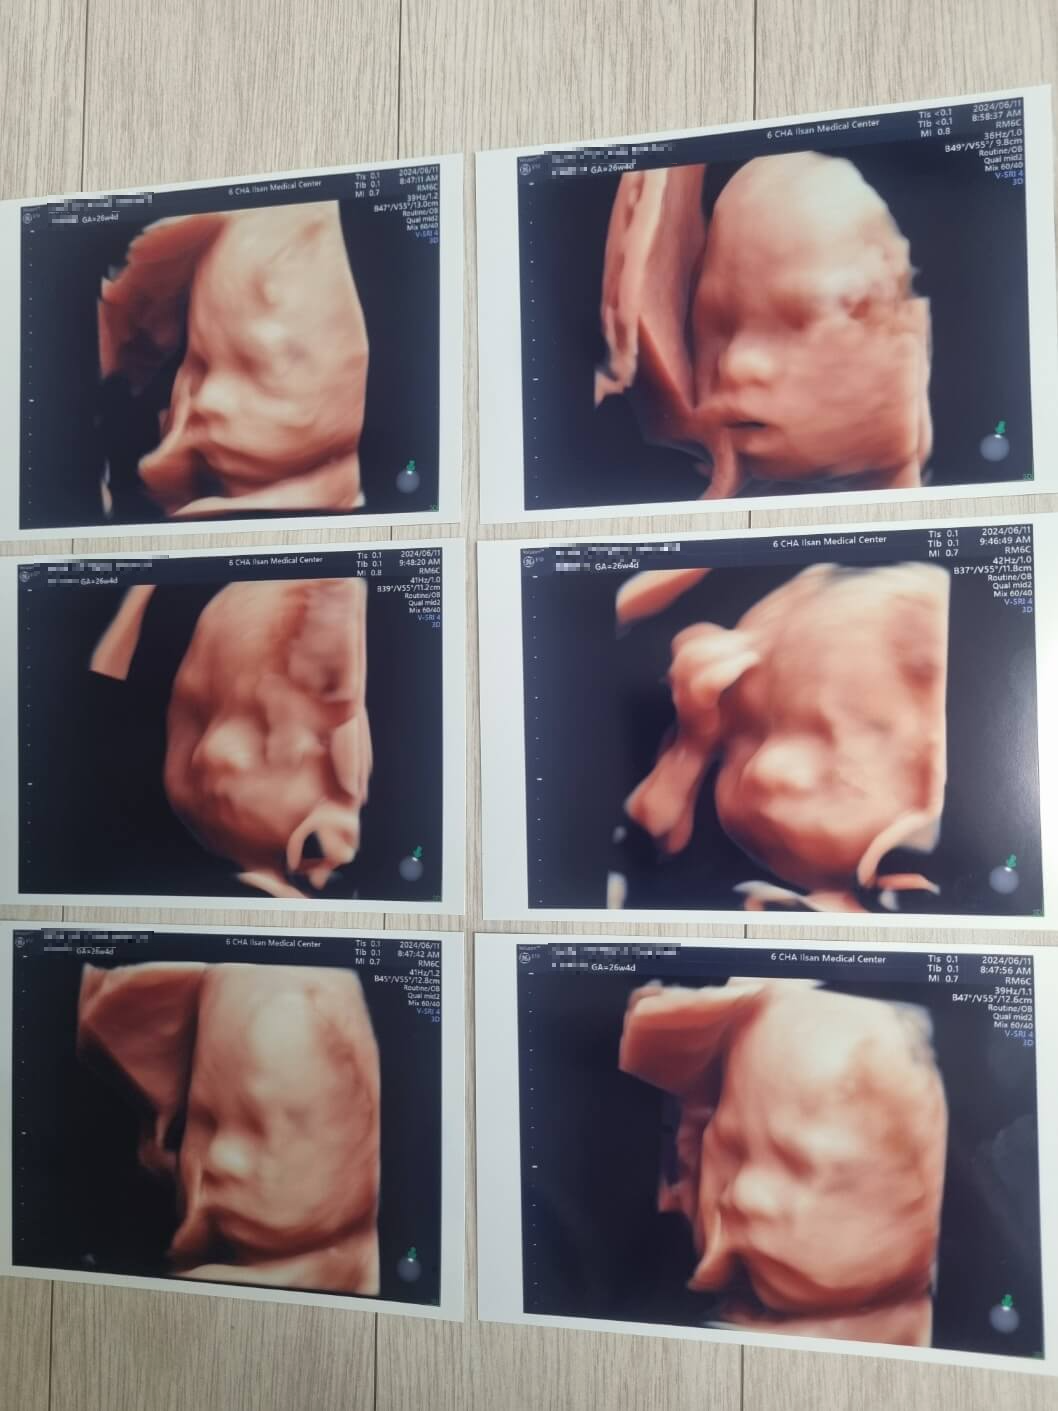

- 입체초음파 사진

♡ 마지막으로 체혈 전까지 우리 아가 입체초음파!!!

너무너무 기대했는데

솔직히 낯설다 ㅎㅎㅎ

누굴 닮은 건지도 모르겠고

그래도 자꾸 보게 되고 신기하다 ㅎㅎㅎ

빨리 만나고 싶다 아가야♡